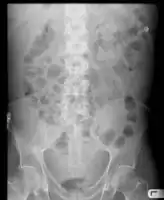

Ascites

Ascites on AXR